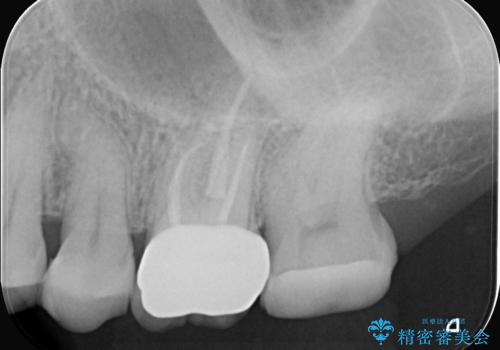

根管治療が完了し、歯の内部が清潔で安定した状態になった後、歯を保護し、強い咬合力に耐えられるよう**クラウン(被せ物)**を装着しました。クラウンは、患者様の希望や咬み合わせの状態に応じて、機能性・審美性に優れた素材を選択し、精密に作製しました。